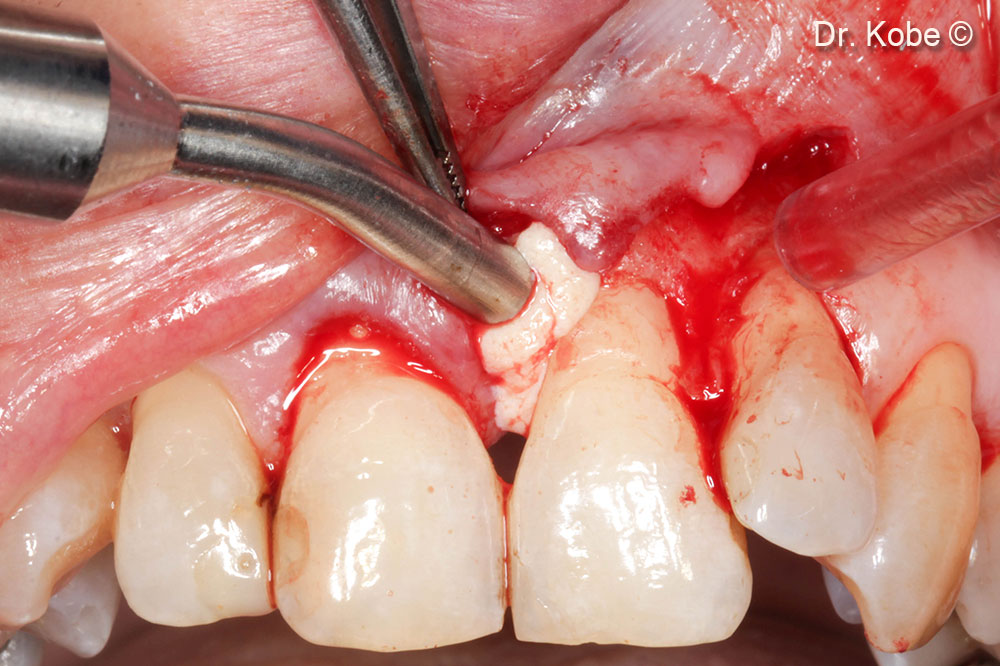

Rạch dọc ở răng liền kề, bảo tồn nhú lợi

Sự hình thành đường hầm ở nhú

Tiếp cận và làm sạch khu vực bị lỗi